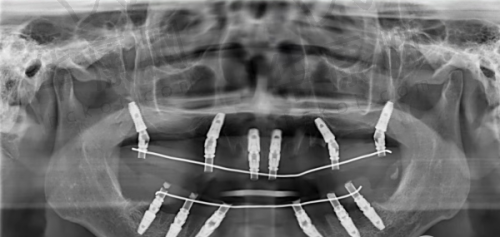

齐齐哈尔美植口腔美国皓圣种植牙3080元起,这一优惠价格吸引了众多缺牙患者的关注。美国皓圣种植牙以其良好的品质和稳定性,成为不少人修复牙齿的选择。而齐齐哈尔美植口腔在种植牙领域有着丰富的经验和专精的技术,为患者提供优质的口腔诊疗服务。

2025年,齐齐哈尔美植口腔的美国皓圣种植牙价格十分诱人。单颗种植方面,美国皓圣ET系列种植牙价格2980元起一颗,美国皓圣SS系列种植牙价格3980元起一颗,美国皓圣MS系列种植牙价格4000元起一颗。此外,还有套餐优惠,如种6颗美国皓圣种植牙套餐34800元起,相当于每颗5800元,比单颗价省了1000多。半口种植牙方面,美国皓圣种植牙半口价格4.5万起,全口价格7万起。与市场上其他机构相比,美植口腔的美国皓圣种植牙价格相对亲民。例如,在其他一些机构,美国皓圣种植牙单颗价格可能在5000 - 10000元左右,而美植口腔3080元起的价格优势明显。

齐齐哈尔美植口腔是齐齐哈尔牙科医院排名前十的口腔机构,在当地有着良好的口碑。医院拥有精良的口腔诊疗设备,这些设备能够为种植牙手术提供精细的诊断和治疗支持。比如,口腔CT设备可以清晰地显示患者口腔内部的骨骼结构和牙齿情况,帮助医生制定更加严谨的种植方案。此外,医院的环境舒适宜人,为患者提供了一个轻松的就诊氛围。从接待区到诊疗室,都经过精心设计和布置,让患者在就诊过程中感受到温馨和舒适。而且,美植口腔还注重服务质量,从患者进门的那一刻起,就有专精的医护人员进行引导和服务,解答患者的疑问,消除患者的顾虑。

美植口腔的医生团队在种植牙领域有着丰富的经验和专精的技术。他们经过严格的专精培训,掌握了精良的种植牙技术。在进行美国皓圣种植牙手术时,医生们能够根据患者的具体情况,如牙齿缺失的位置、牙槽骨的条件等,制定个性化的种植方案。例如,对于牙槽骨条件较差的患者,医生可以采用骨增量技术,增加牙槽骨的厚度和密度,为种植牙提供更好的支撑。此外,医生们还注重手术的安心性和精细性,在手术过程中,会严格遵守操作规范,确保手术的顺利进行。而且,美植口腔的医生团队还会定期参加学术交流和培训活动,不断学习和掌握全新的种植牙技术和理念,为患者提供更加优质的服务。